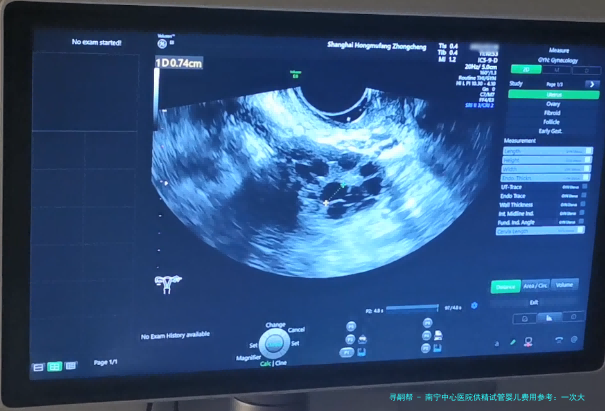

通过注射促排卵药物,刺激卵巢内多个卵泡发育成熟。 3.采卵手术:

在超声引导下,通过微穿刺方式取出成熟的卵子。 4.精子和卵子结合培育胚胎: